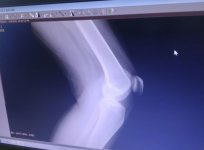

ركبتي تؤلمني يشدة عند صعود الدرج والانحناء ودكتور العظام والمفاصل فقط فحص الليونة لم يفحص الركبة واراد التاكد من وجود خشونة وطلب مني صور اشعة لكن صورتها بالموبايل من المشفى الحكومي وعندما راى الصور اخبرني انها مجرد ليونة وتختفي مع قيامي بتمرين 50 مرة في اليوم لشهرين اريد التاكد هل احتاج للمزيد من اجل التشخيص وشكرا

- ليونة ركبة فقط